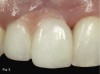

A 38-year-old Caucasian female patient presented with a high smile line and loss of the papilla between tooth No. 7 and edentulous adjacent site No. 8 (Figure 1). Understandably, the patient was unhappy and embarrassed about her esthetic condition. Her dental history revealed tooth replacement of No. 8 with an implant that eventually failed. The site had been previously bone grafted upon implant removal. She was given a composite pontic No. 8 bonded to a tooth No. 7 composite veneer as a transitional restoration. The implant was positioned too close to the proximal surface of tooth No. 7, which stripped the periodontal attachment of the root and ultimately caused loss of the papilla (Figure 2). As previously outlined, the treatment sequence would be to first provide a provisional restorative solution to evaluate the projected outcomes and assess if the patient was willing to undergo orthodontic therapy. In this situation, a full-coverage crown No. 7 with a cantilevered pontic No. 8, with artificial acrylic gingiva to replace the lost papilla on the mesial aspect of tooth No. 7 was used as a transitional temporary prosthesis (Figure 3). In addition, a composite resin restoration was placed on the mesial aspect of tooth No. 9 to restore its individual tooth proportion and shape. The patient’s esthetic outcome could now be evaluated with restorative correction alone; it was therefore mutually determined that the correction of her deformity would best be served with additional orthodontic forced eruption therapy. A fixed orthodontic appliance (brackets) was bonded to the teeth and temporary prosthesis. The level of the interproximal pink acrylic was used as a therapeutic guide for the amount of forced eruption required as well as the alignment of the mesial papilla of No. 7 to that of the adjacent papillae height (Figure 4). Floss was used to elevate the amount of vertical movement achieved relative to the adjacent papilla tooth No. 9. Eventually, all the artificial pink acrylic was removed. (Note that the distal papilla on tooth No. 7 also comes more incisal—in fact, it is slightly excessive at the endpoint of treatment [Figure 5]). However, the distal papilla and midfacial tissues of tooth No. 7 can be reshaped through clinical crown lengthening toward the end of treatment prior to definitive restoration, thereby restoring the proper papilla height-to-tooth ratio of 40%. After stabilization of tooth No. 7 for a minimum of 6 months post-orthodontics, an implant was placed in site No. 8. A papilla-sparing incision design was used for flap elevation (Figure 6), bone allograft was used to further augment the facial aspect of the ridge simultaneously with implant placement (Figure 7), and a resorbable membrane was used for guided bone regeneration.

Fig 7. A bone allograft was placed to augment the labial aspect of ridge No. 8 during simultaneous implant placement.

Figure 7